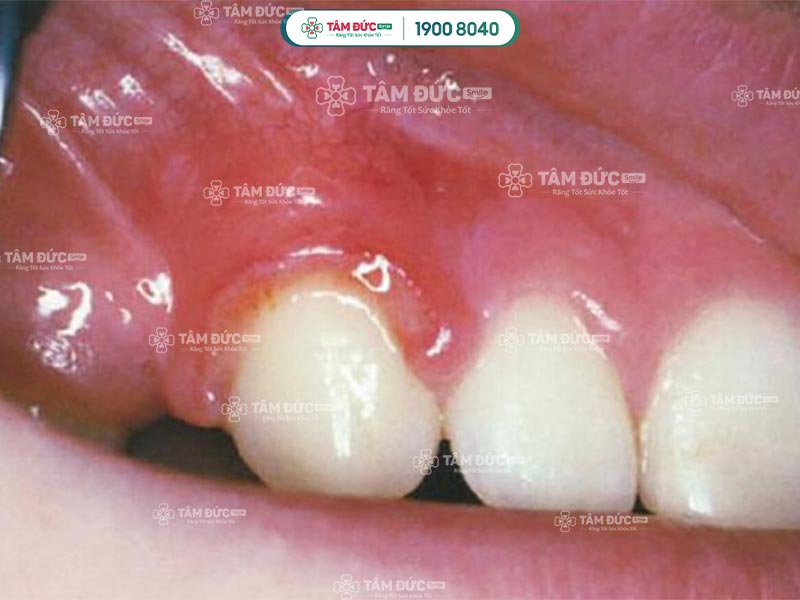

Viêm nướu chân răng do bị chấn thương

1.2.6. Bọc răng sứ kém chất lượng

Bọc răng sứ kém chất lượng chẳng những không bảo vệ được răng mà còn làm tăng nguy cơ viêm nướu chân răng. Đó là các dòng răng sứ có pha lẫn kim loại dễ kích ứng mô nướu và dẫn đến viêm nhiễm.

Ngoài ra, khi kỹ thuật mài răng không tốt sẽ làm mòn men răng, tổn thương ngà răng và dễ làm cho vi khuẩn xâm nhiễm vào trong răng.